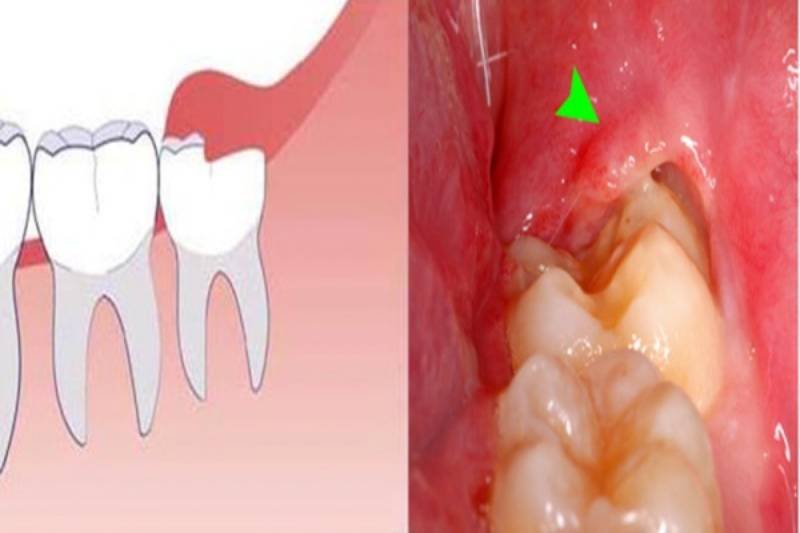

Lợi trùm hay lợi trùm răng khôn là tình trạng bao phủ lợi lên răng, có thể một phần hay toàn bộ răng, phần lợi này gây cản trở phát triển hay mọc răng của răng khôn.

Do răng khôn nằm ở nơi sâu nhất, nên rất khó để vệ sinh. Lâu ngày sẽ tích tụ vi khuẩn làm cho phần lợi trùm bị viêm nhiễm, gây cho bạn đau nhức, khó chịu,… Lúc này việc cắt lợi trùm là điều rất cần thiết